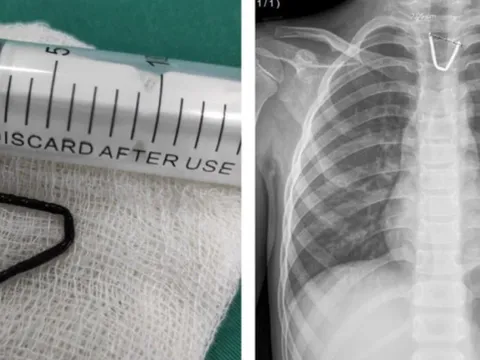

Hoảng hồn khi thấy đoạn kim khí sắc nhọn mắc trong họng bé 8 tuổi

Mới đây, Trung tâm Y tế huyện Tân Sơn (Phú Thọ) vừa thực hiện thành công ca can thiệp lấy dị vật thực quản là đoạn kim khí hình chữ U ra khỏi thực quản bé gái 8 tuổi.